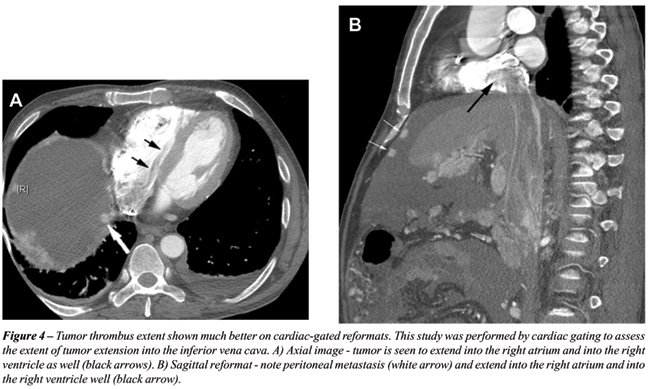

Contiguous thin sections are obtained using protocols dependent on machine manufacturer to enable overlapping reconstruction. At our institution, multiphase CT scans are obtained on GE Lightspeed VCTTM 64 slice scanner at 0.625 mm thickness at a pitch of 1.375:1. These slices are reconstructed at 2.5 mm thickness in the axial plane and coronal reformats are obtained at 5 mm intervals. Sagittal reformats and 3D reconstruction are performed on a case specific basis. Cardiac gated studies are performed for patients with IVC extension (see Figure-4). Multi-phase CT of the abdomen is performed from top of the liver to 1 cm below the lowest kidney. A 15 minute scanogram is performed at the end of the exam to assess the ureters. The protocol used at our institution is illustrated in Table-1.

With the rapid acquisition of multiple simultaneous slices and thin-section reformatted coronal and/or sagittal images, the 64-slice CT scanner provides excellent detail in demonstrating local extension to the bowel and retroperitoneum (see Figures-2, 3, 5, 6 and 7). Multiplanar three-dimensional reconstruction techniques including volume rendering, maximum intensity projection and shaded surface display provide comprehensive information about the relationships and possible involvement of vascular structures in renal neoplasms.

64 slice CT imaging provides an improvement in the preoperative analysis of renal masses. The reformatted images in multiple planes and cardiac-gated sequences can offer additional help in surgical planning and reformatted images provide detailed information about arterial and venous collaterals and invasion of adjacent organs.